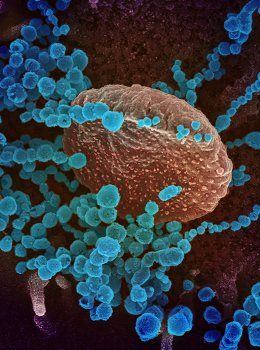

The Wonderful World of 3D+